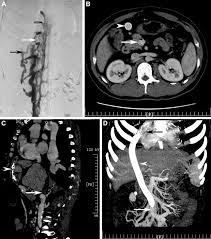

Chiasmata -mə-tə or chiasmas also chiasms 1. Esophageal varices are extremely dilated sub-mucosal veins in the lower third of the esophagus. Located in metro Denver northern Colorado and western Nebraska serving all of the Front Range our team consists of board-certified and fellowship-trained interventional radiologists. This results in hepatic congestion similar to Budd-Chiari syndrome and post-sinusoidal portal hypertension. The patients condition should be monitored throughout the procedure. They are most often a consequence of portal hypertension commonly due to cirrhosis. Toxic injury to liver sinusoids causes sloughing of endothelial cells that embolize to hepatic venules and cause eventual fibrosis of the venules. Coin in the Esophagus. There is no clear consensus regarding the number of occluded veins some authors claim that there should be at least one occluded hepatic vein 7 others state that there are no significant.

Carcinoma of the Colon. Budd-Chiari syndrome a blockage in one or more veins that carry blood from the liver back to the heart. And coumarin skin necrosis adrenal gland hemorrhage and infarction. Toxic injury to liver sinusoids causes sloughing of endothelial cells that embolize to hepatic venules and cause eventual fibrosis of the venules. Chiari malformation CM is a structural defect in the cerebellum characterized by a downward displacement of one or both cerebellar tonsils through the foramen magnum the opening at the base of the skull. Embolism and thrombosis of. La présence dune ou plusieurs affections prothrombotiques est fréquente La prise en charge repose sur un traitement anticoagulant précoce le traitement de l.